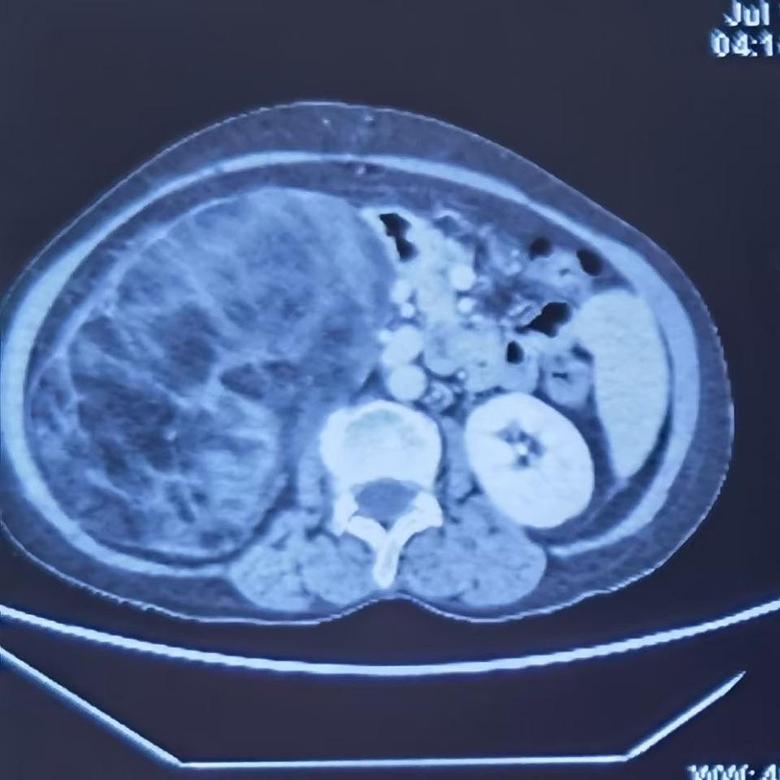

病例2

今日下午,2例巨大腹膜后肿瘤手术在我科顺利开展,腹膜后肿瘤发病率低,手术难度大,手术风险大,国内开展相关手术单位为数不多,我院腹膜后肿瘤手术量连续数年位居国内前列,在腹膜后肿瘤领域团队具有丰富经验,巨大腹膜后肿瘤手术开展,表明该类手术在我院已经成为常态。并且将继续保持国内在领先水平。